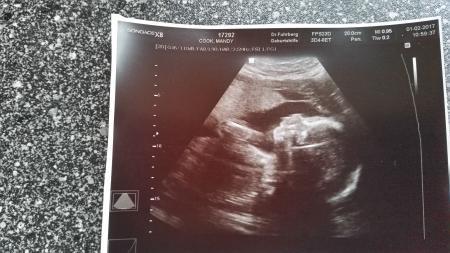

Hallo Mädels Heute hatten wir den nächsten Gyntermin.Unserem Jungen geht es gut. Herzschlag ist gut und er ist zeitgemäß gut entwickelt.er wiegt 750Gramm und ist 32,2cm lang.

Bild zu 25SSW bald rum :-) - Forum für Mai - Mamis